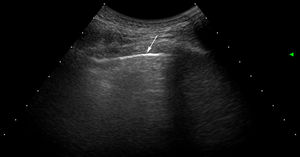

Ultrasound scan interpretationThe basic finding to be evaluated by US is the B line, which is defined as a hyperechoic narrow base reverberation artefact, which extends like a laser beam until the edge of the screen. These B lines are generally not present in the lungs of healthy subjects16,17 (Fig. 1). In each intercostal space (IS) the number of B lines was recorded, and subsequently the total number of all of the B lines found by pulmonary US was registered and classified using the semi-quantitative scale proposed beforehand (0 = normal, ≤ 5 B lines; 1 = mild, ≥ 6 and ≤ 15 B lines; 2 = moderate, ≤ 16 and ≥ 30 B lines; 3 = severe, ≥ 30 B lines). The above operation was performed for the purpose of correlation with HRCT findings.

US images showing different signs of ILD based on the number of B lines.

A. There is only one B line (arrowhead). B. 4 B lines are visible (arrowheads). Pleural irregularity is present in both cases (arrows). C. US image showing an intercostal space with 6 B lines and net pleural irregularity in comparison with the HRCT image of ILD (D).